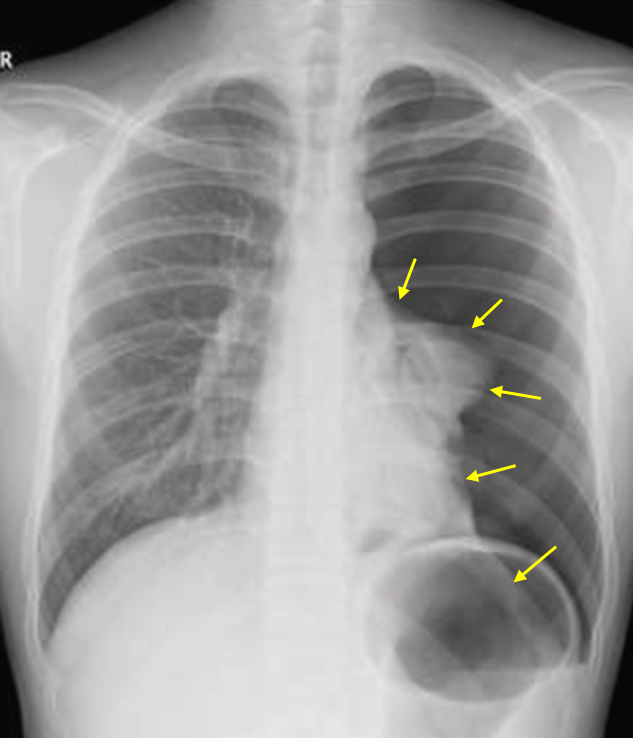

18세 남자가 2일 전부터 왼쪽 가슴이 아프고 숨이 차서 병원에 왔다. 2일 전 축구를 하던 중에 왼쪽 어깨와 등 부위에 통증이 발생하였고 점점 숨쉬기가 어려워진다고 한다. 기저 질환이나 외상력은 없다. 혈압 126/88 mmHg, 맥박 78회/분, 호흡 30회/분, 산소포화도 93%이다. 가슴 X선사진이다. 치료는?

Img | CXR: Lt. total pneumothorax |

CXR상 감압이 필요한 정도의 기흉이 확인되며, 진행성 호흡곤란 및 tachypnea를 보이고 있으므로 흉관 삽입을 시행한다.

• CXR상 실제로 Lt. lung이 total collapse되어 있는 기흉이 보인다. 10대의 젊은 환자에게서 명확한 외상력(축구를 하고 있던 중 발생했다고 하나, 외상력은 없었다고 함) 없이 발생했으므로 primary spontaneous pneumothorax로 보는 것이 적절하다.

• RR > 24로 빠르고, total lung collapse가 될 만큼의 기흉이 있으므로 흉관 삽입이 필요하다. 흉관 삽입은 폐쇄성 가슴관 삽입술(closed thoracostomy)이라고도 부른다.